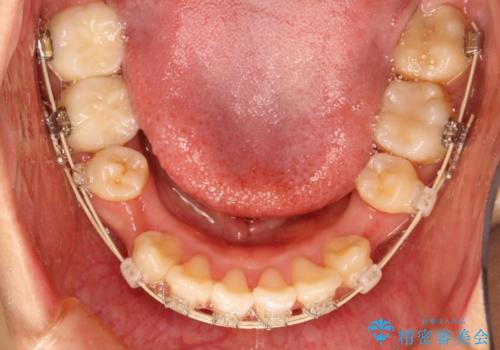

上下の歯のガタガタ ワイヤーでの抜歯矯正で整った歯並びへ

- 矯正装置

- 審美装置

- 上下の歯のガタガタを治したいとのことで来院されました。

がたつきの度合いが強いのと、口元をなるべく引っ込めたい希望がありましたので、ワイヤーでの抜歯矯正となりました。